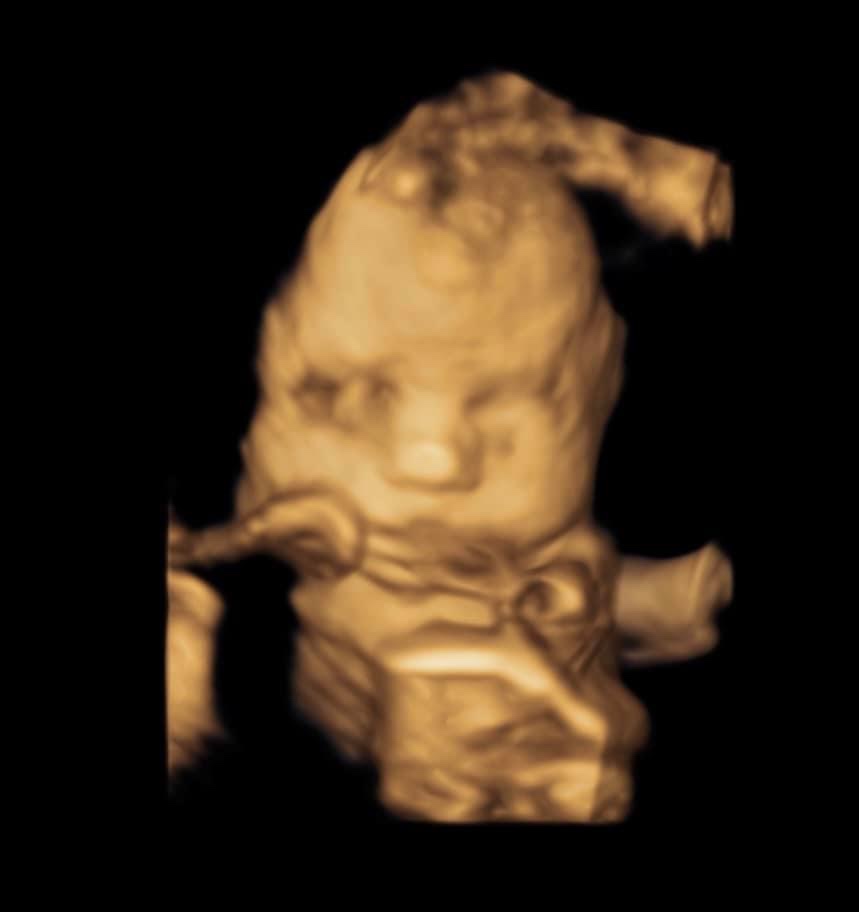

Amelia lived 38 weeks, 5 days in my womb and she lived 11 days after she was born. We are forever changed for having known and loved her.